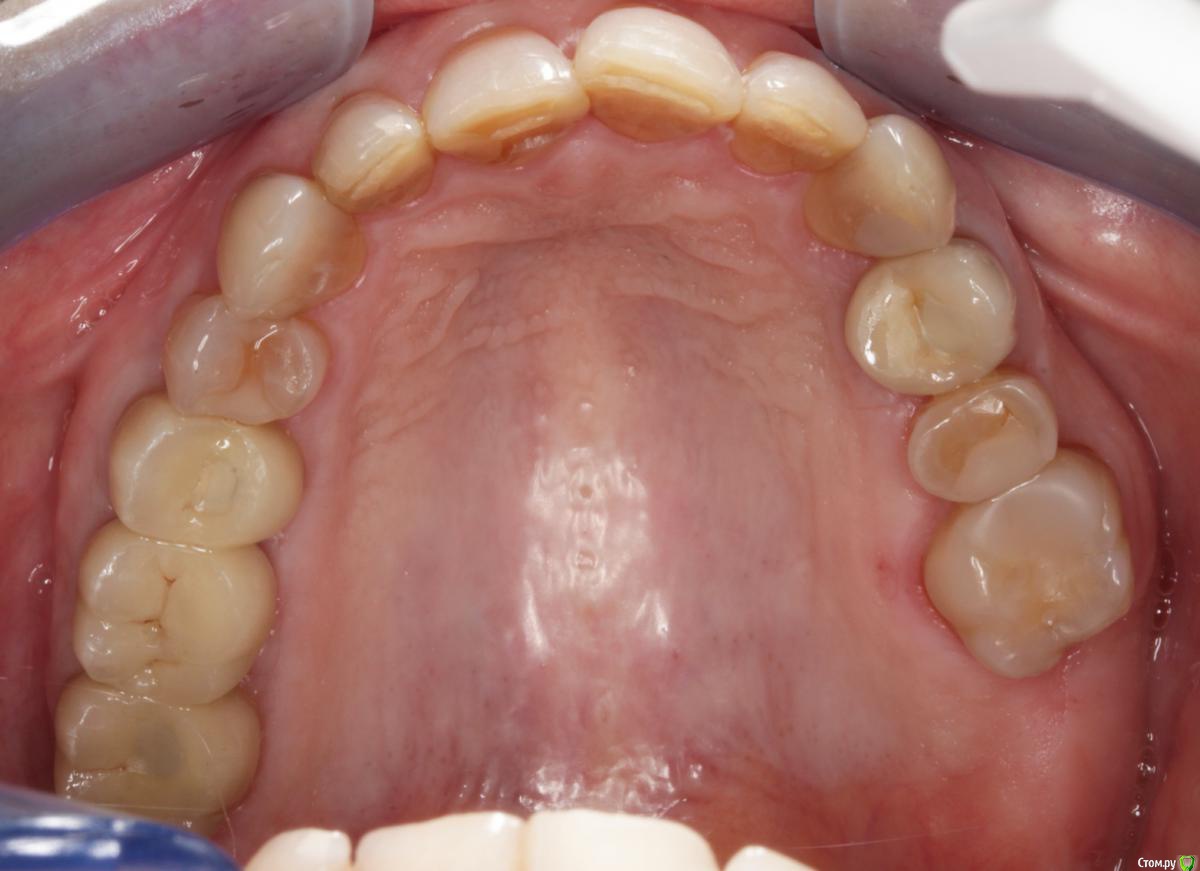

Пациентка пришла с целью восстановления отсутствующих 15,16,17,24,27 з.

Из анамнеза - хронический двухсторонний синусит, соответствующие зубы удалены более 5-ти лет назад, тетрациклиновые зубы ( от изменения цвета отказалась ).

1) имплантация в позиции 15,17 з с закрытым синусом и незначительной НКР

2) коррекция слизистой в области 1-го сегм